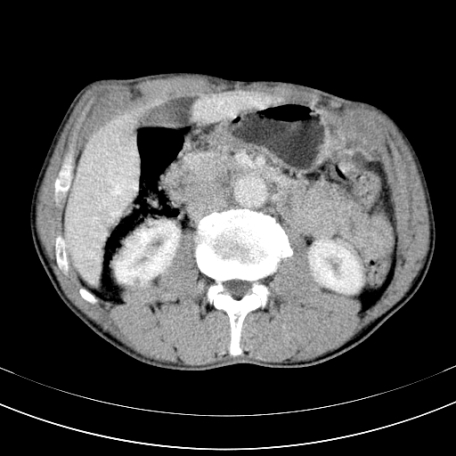

标题: CT21441:男55岁,上腹部胀痛半年余,请老师们看看是后腹膜淋巴 [打印本页]

标题: CT21441:男55岁,上腹部胀痛半年余,请老师们看看是后腹膜淋巴

腹主动脉右侧有一个,有肿瘤病史吗?

转移瘤或淋巴瘤

腹膜后淋巴结肿大,原因待查。